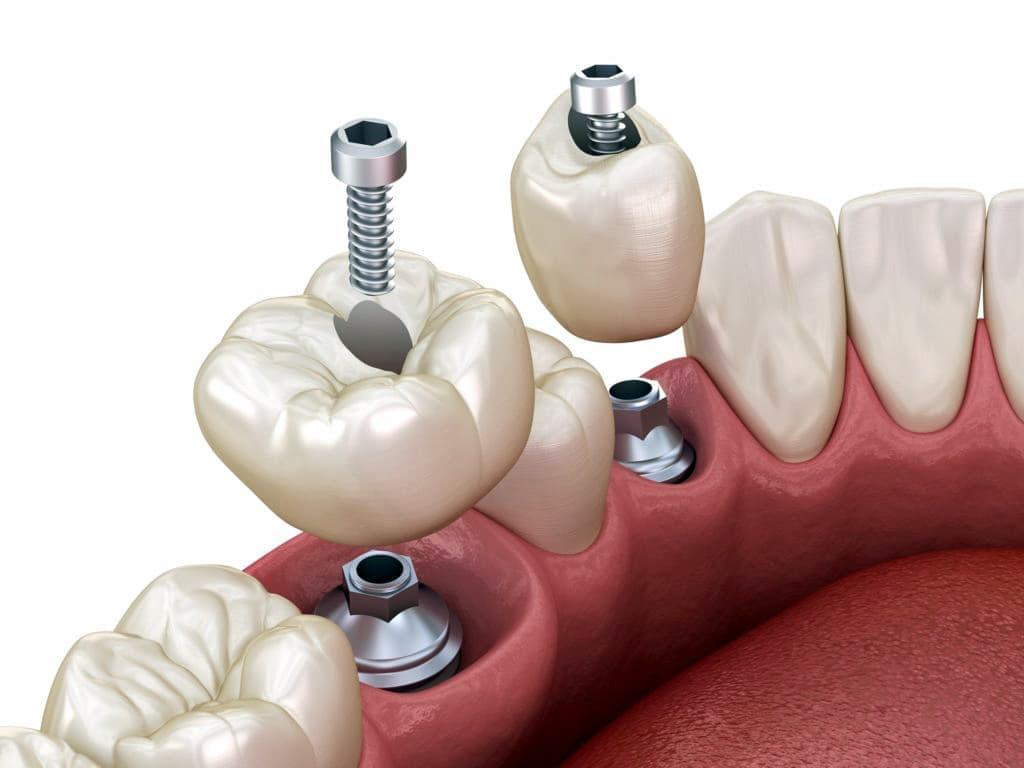

インプラントとは、顎の骨に人工歯根となる金属を埋め込み、その金属を土台にして、天然の歯と同じような人工の歯を取り付ける治療方法です。

埋め込む金属に生体との親和性が高いチタンが使われる事が多く、チタンは長年の臨床研究でインプラントの素材として最も安全であり、また顎の骨としっかり結合することが確認されています。